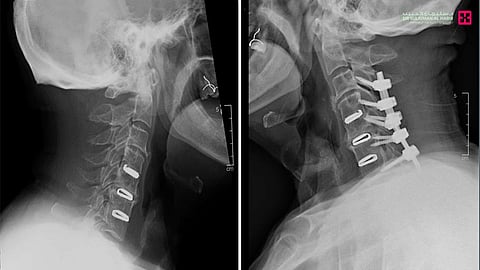

وقال د. محمد السفياني استشاري جراحة العمود الفقري للكبار والأطفال، رئيس الفريق الطبي المعالج، أن المراجع كان يعاني أيضاً من مشاكل صحية مزمنة بالقلب، وأخضع لحزمة من الفحوصات الطبية الدقيقة، بدأت بالكشف السريري لتحديد طبيعة الإصابة وموقعها وحدتها، ثم بعض الفحوصات المخبرية، بالإضافة إلى التصوير بالأشعة السينية X ray، والأشعة المقطعية CT scan لتبيان حالة الفقرات العظمية للعمود الفقري، وكذلك الرنين المغناطيسي Mri للرقبة لفحص الأقراص الغضروفية بين الفقرات، وأظهرت النتيجة وجود خشونة وانزلاقات غضروفية ضاغطة بشدة على الحبل الشوكي في منطقة الفقرات الرقبية، وأيضا بين التخطيط العصبي وجود ضغط شديد بالنفق الرسغي باليدين، وناقش الفريق الطبي الحالة على ضوء معطيات التشخيص، مع وضع الحالة الصحية العامة للمراجع في الاعتبار، لاسيما وأن التخدير العام يمثل عامل خطورة عليه لإصابته بمشاكل صحية مزمنة بالقلب، وفي النهاية خلص الفريق الطبي إلى خطة علاجية، وأُجرى للمراجعة عمليتين بوقت واحد تم فيها تحرير العمود الفقري من الضغط بإزالة الانزلاق الغضروفي وتثبيت الفقرة الرقبية رقم "٣" وتوصيلها للفقرة العنقية السابعة، تحت جهاز المراقبة العصبية، واستمرت العملية لنحو "3 ساعات، وبعد ذلك إجراء جراحتين باليد اليمنى واليسرى لتحرير النفق الرسغي ومضت العملية بسلاسة وانتهت ولله الحمد بالنجاح التام، ونقل المراجع من غرفة العمليات إلى غرفة التنويم، حيث أمضى "5" أيام تحسنت حالته خلالها مع الرعاية الطبية الحثيثة، كما أنه أستعاد قدرته على المشي بعد نحو "36" ساعة من العملية، وغادر المستشفى بحالة صحية ممتازة، وقد تخلص من الأعراض التي جاء بها بسببها إلى المستشفى، فتحرر من قيود ضعف الحركة وعاد لممارسة حياته بصورة طبيعية وبلا آلام.